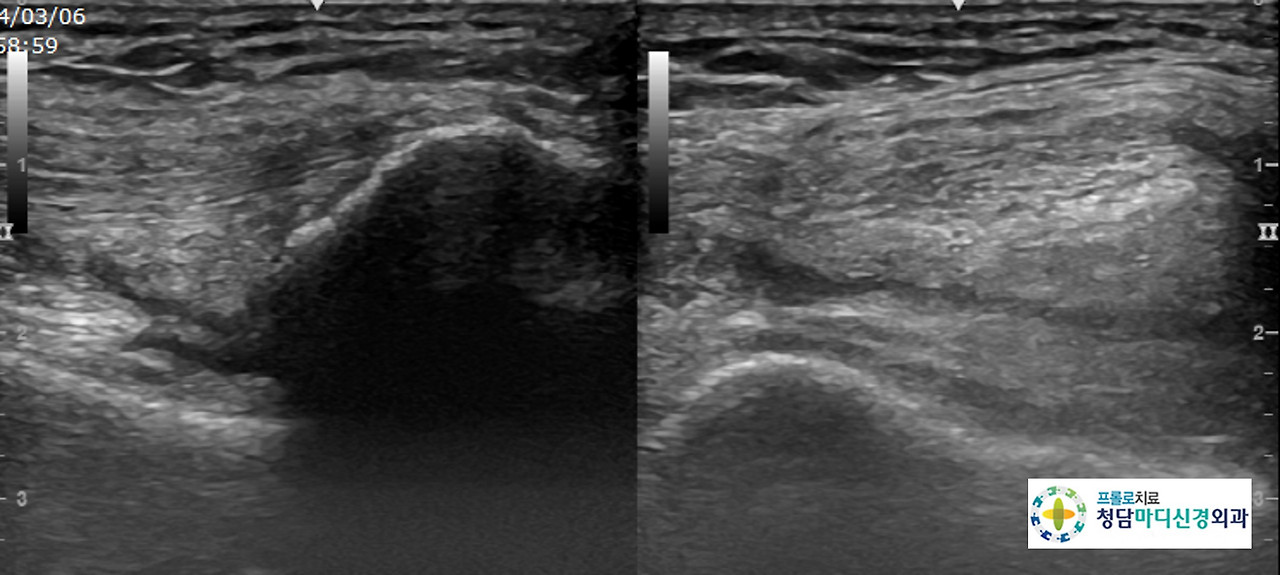

0516(3).jpg 무릎 초음파 사진

0516(4).jpg 무릎 초음파 사진

초음파 검사상에는 관절낭에 삼출액이 보이고, 대퇴골과 하퇴골의 골극을 보이면서 연골간격이 좁아진 소견을 나타냈습니다.